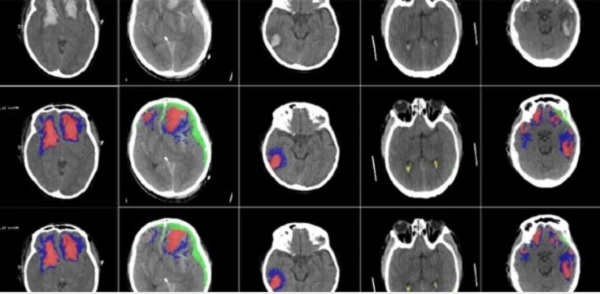

Các nhà nghiên cứu đã phát triển một thuật toán AI có thể phát hiện và xác định các loại chấn thương trong não.

Các nhà nghiên cứu, từ Đại học Cambridge và Đại học Hoàng gia Luân Đôn, đã xác nhận lâm sàng và thử nghiệm AI trên các bộ quét CT lớn và thấy rằng Al có thể phát hiện, phân đoạn, định lượng và phân biệt các loại tổn thương khác nhau trong não.

Các nhà nghiên cứu đã phát triển một công cụ học máy học dựa trên mạng lưới thần kinh nhân tạo. Họ đã đào tạo công cụ này trên hơn 600 lần chụp CT khác nhau, cho thấy các tổn thương não có kích cỡ và các loại khác nhau. Sau đó, họ xác nhận công cụ trên một bộ dữ liệu lớn về quét CT.

AI có thể phân loại từng phần riêng lẻ của mỗi hình ảnh và cho biết nó có bình thường hay không. Điều này có thể có ích cho các nghiên cứu trong tương lai về cách tiến triển của chấn thương đầu, vì AI có thể phù hợp hơn so với con người trong việc phát hiện những thay đổi tinh tế theo thời gian.